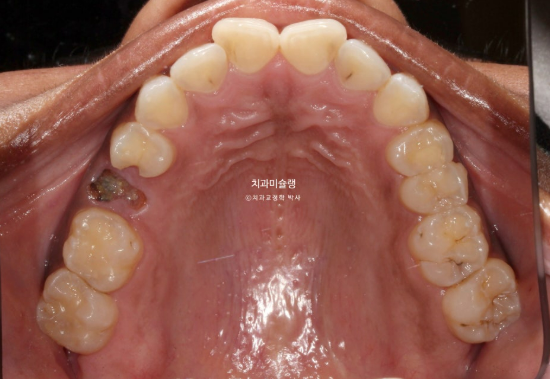

In the maxilla, one premolar had decayed to the point where only the root remained.

In cases where a premolar is missing like this, if protrusion or crowding is present, we can proceed as if premolar extraction had already been performed. By extracting other compromised premolars and utilizing the extraction spaces, we can resolve crowding and protrusion simultaneously. This approach is advantageous, as premolar extraction is often indicated in such cases, and it eliminates the need for implants.

On the opposite side, there was a tooth that had undergone root canal treatment and had been temporarily restored. We decided to extract this tooth.